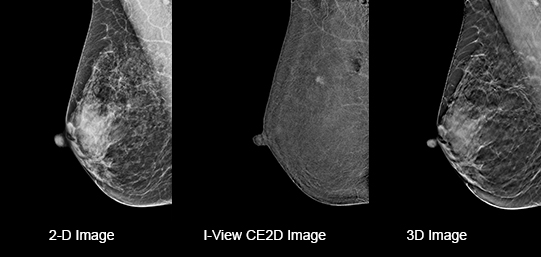

Eliminates Structural Background

Acquire a pair of high- and low-energy images in rapid succession. This allows for regions of abnormal blood flow to be displayed by subtracting the background breast parenchyma.

Contrast-enhanced mammography enhances visualization and may uncover hidden abnormalities – a crucial factor in reducing missed and or underdiagnosed cancers.